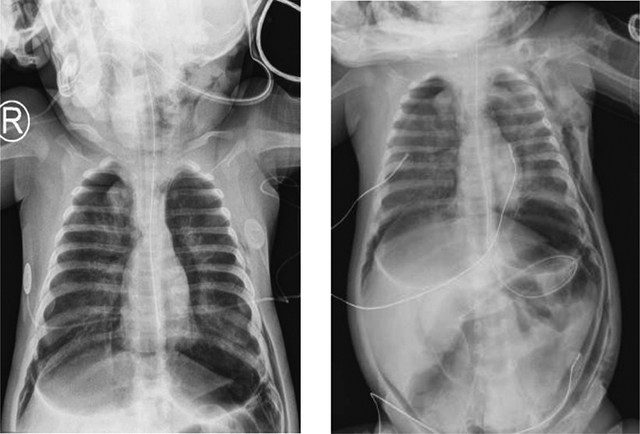

Mechanical ventilation was performed to improve the patients episodes of apneas and desaturation but resulted shortly after in free air located at the infra-thoracic part of the chest radiograph (Figure 3A and B), treated by the placement of two left thoracic drains.

Figure 3

(A, B) Chest and abdominal antero-posterior radiograph.

Free air (subcutaneous emphysema) located at the infra-thoracic part of the chest radiograph.